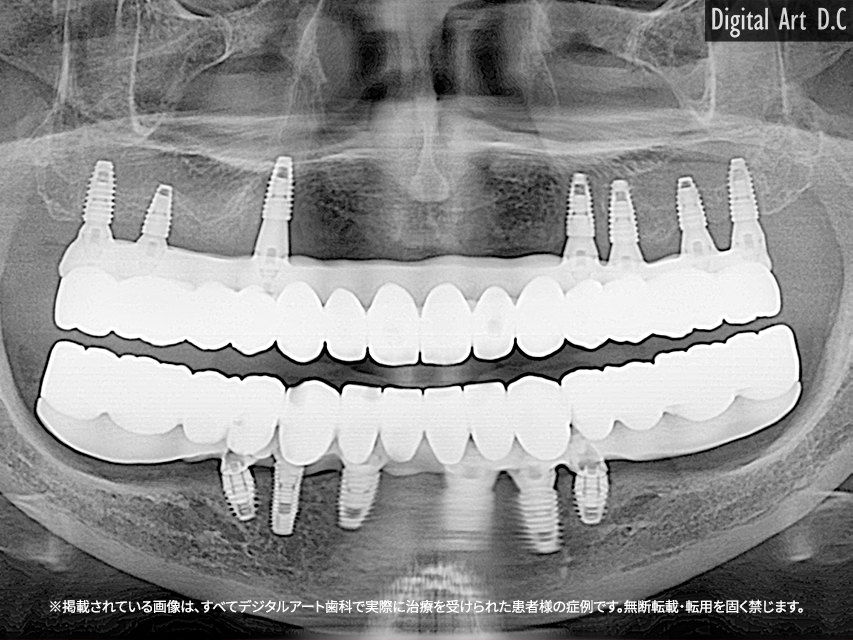

- All-on-4 / All-on-6 방식: 4~6개의 임플란트로 전체 보철물을 지지

- 하이브리드 보철 방식: 고정과 탈착식이 결합된 형태

- 초기 상담 및 3D CT 정밀 진단

- 임플란트 식립 및 임시 보철 장착

- 잇몸 회복 기간 (약 2~4개월)

- 최종 보철물 제작 및 장착